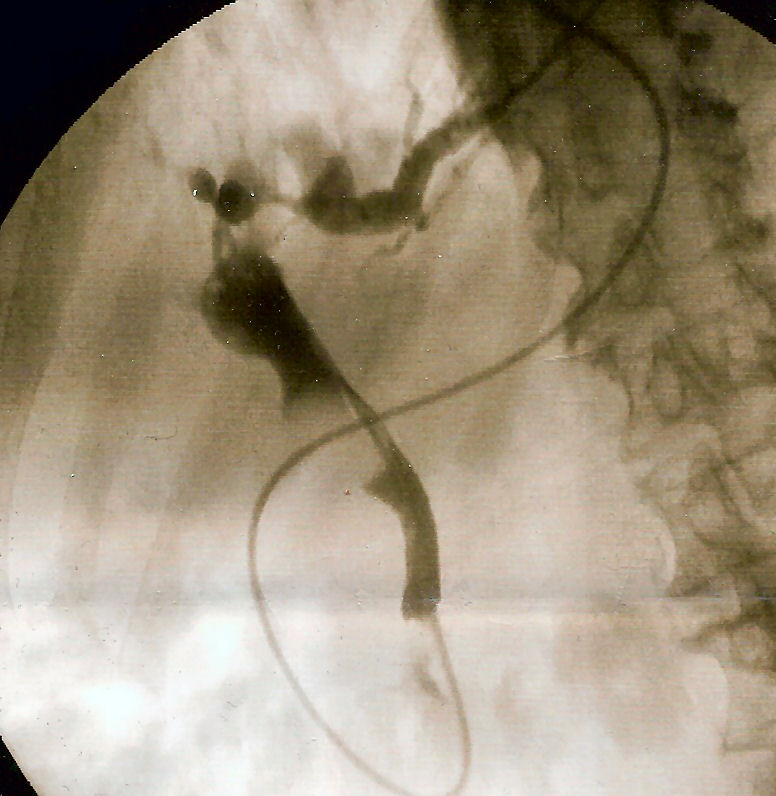

Ascending Cholangitis

Ascending cholangitis is a bacterial infection of the bile ducts.

Ascending cholangitis is typically brought on by an escalating gram-negative intestinal infection.

Symptoms of ascending cholangitis include:

- Stomach discomfort

- Jaundice

- Sepsis

There is a higher prevalence of choledocholithiasis (stone in biliary ducts) in ascending cholangitis.